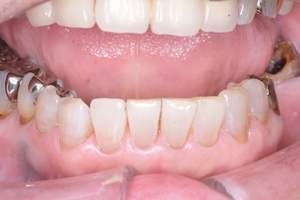

治療前 1

治療後 1

治療前 2

治療後 2

治療前 3

治療後 3

| 年齢 | 58歳・女性 |

|---|---|

| 主訴 | 前歯の着色除去希望 |

| 治療内容 | エアフロー |

| 費用 | 合計:5,500円 (2024年8月現在) |

| 治療期間 | 60分 |

| リスク・副作用 | 呼吸器疾患のある方や放射線治療を行っている方、ナトリウム摂取制限を必要とする方や妊娠中の方は処置を受けられないことがあります。 施術を受ける際、舌や歯肉に当たった粒子でチクチクとした痛みを感じることがあります。 |

| 治療方針 | 歯周病と虫歯の治療を担当医と相談し進めていく予定です。 |

| 担当者所見 | 約4年ぶりの来院でした。他の歯医者に行っても満足いくクリーニングをしてもらえず悩んでいる様子でした。問診時には手で口元を隠すようにお話されていましたが、エアフロー後は笑顔でお話するようになっていました。 |